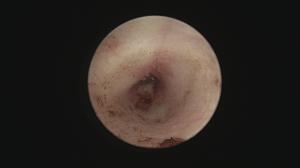

今回は右の耳内がグチュグチュしている猫ちゃん。

原因不明で来院されました。

耳内をキレイにして内視鏡で覗いてみると・・・

これはポリープですね

このような場合、根元は鼓膜の奥、中耳内から発生していることが多いです。

耳内の不快感、化膿はこれがあるためですね!